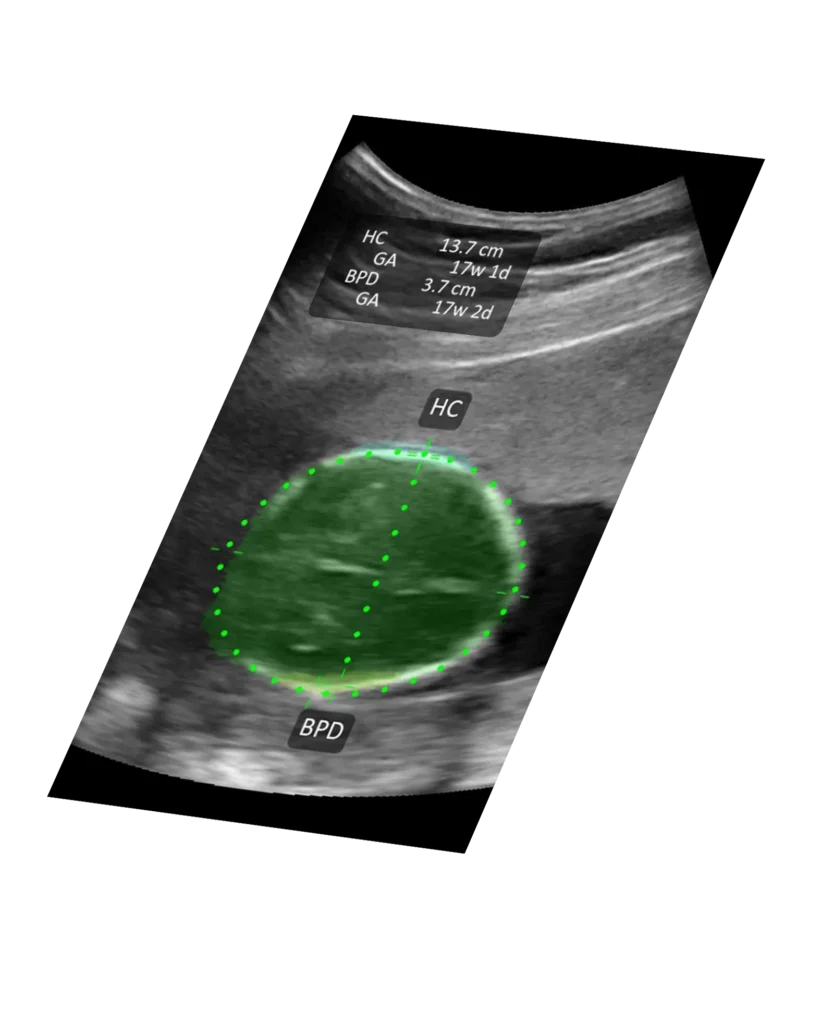

T-Mode™ teaches as you scan. Instantly see labeled anatomy, so even novice users can interpret images and make decisions with confidence.

Key anatomical structures are automatically highlighted and labeled to reduce interpretation time.